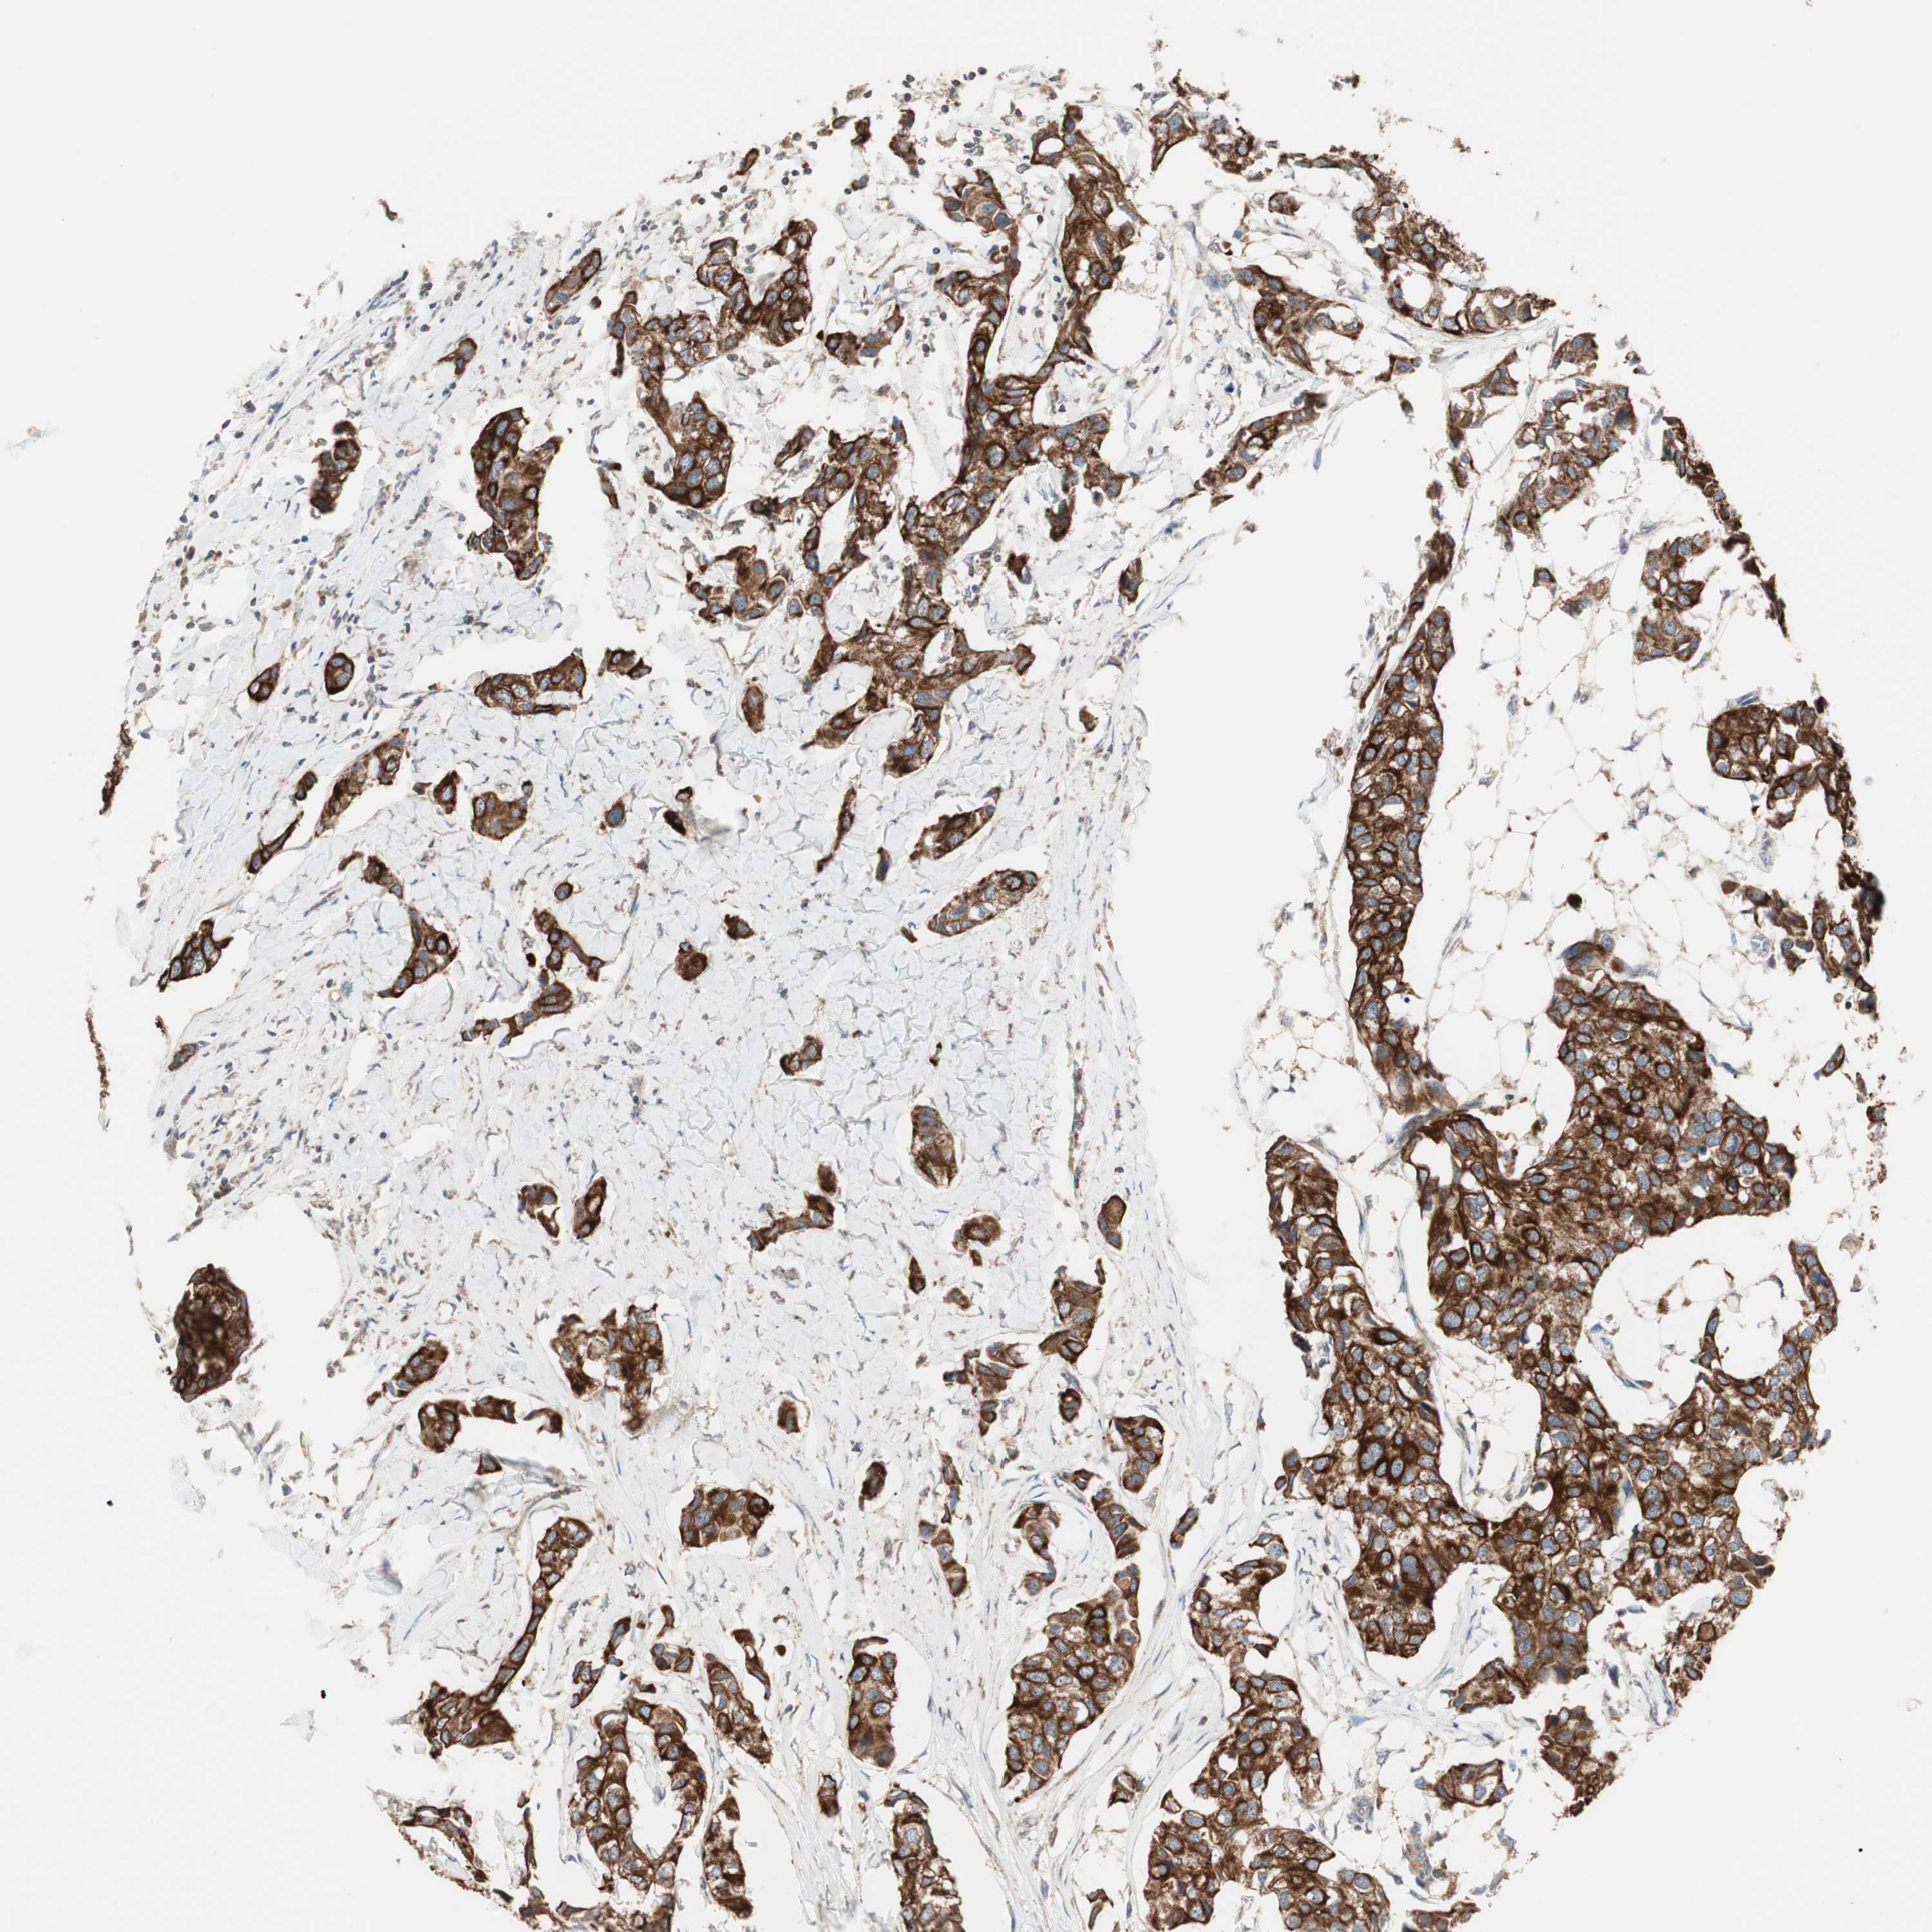

CANCER BREAST CANCER Show tissue menu

BRCA TCGA BRCA VALIDATION PROTEIN EXPRESSION